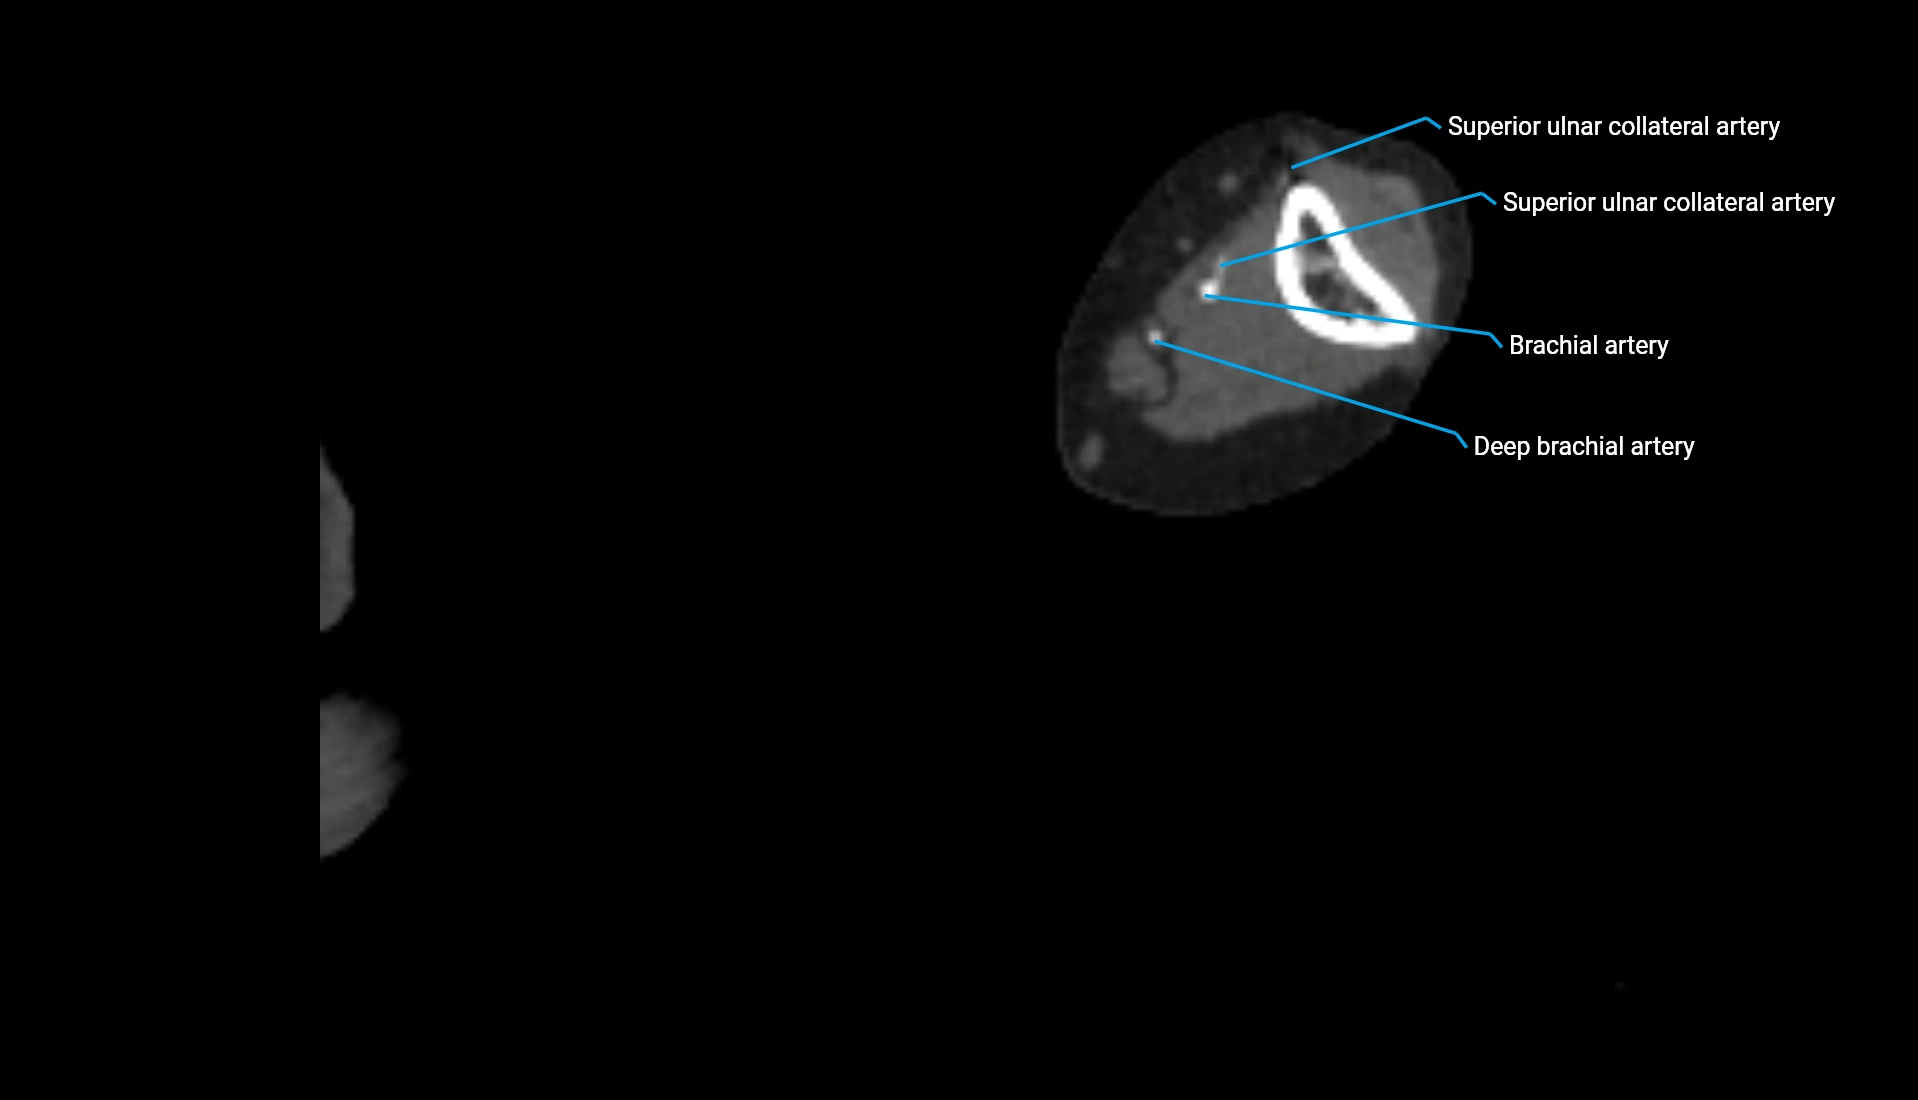

CT Appearance

Post-Contrast CT:

• Bone: No enhancement

• Joint capsule and synovium: Mild enhancement outlining the joint

• Improves contrast between soft tissues and bony margins

• Useful in detecting subtle joint abnormalities or postoperative changes